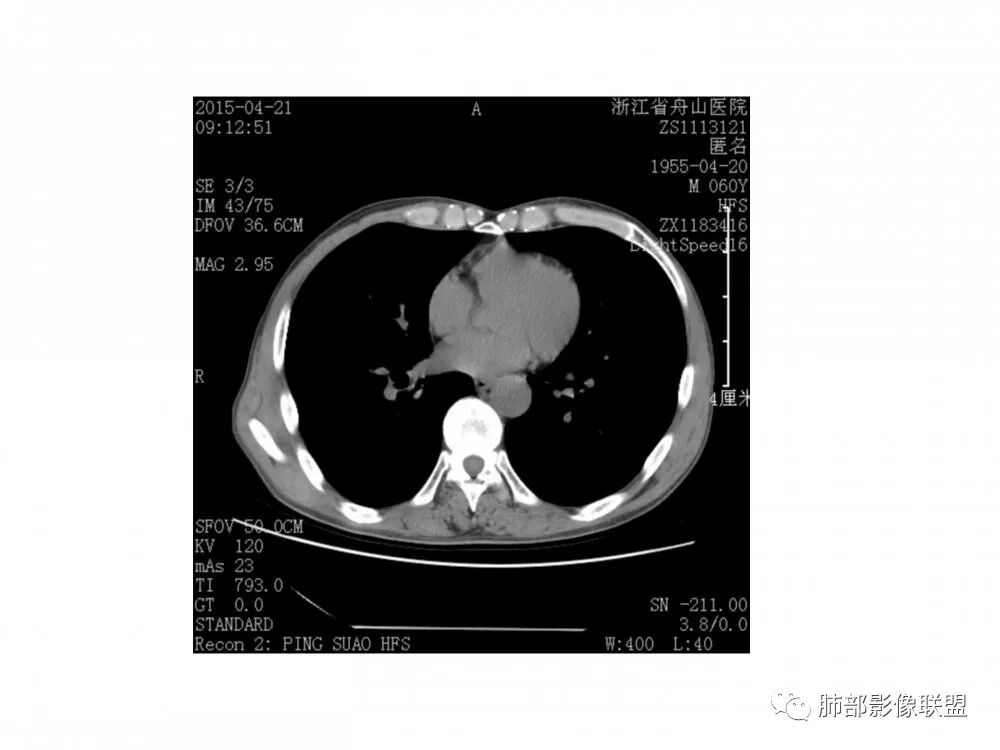

老年男性,60岁,右下肺门肿块,右下支气管粘膜下生长,并堵塞,无明显阻塞性肺炎和肺不张,早期多发淋巴结转移,似不均匀强化。综合看恶性程度高,考虑大细胞癌,一个不支持点,大细胞癌外周多见。

老年男性,右下基底外压狭窄,11、10、7、4、2组淋巴结肿大,考虑小细胞

老年男性,右下支气管新生物,像粘膜下生长,气管软骨似乎破坏不明显,无阻塞性炎症,纵隔淋巴结肿大;考虑恶性并淋巴结转移可能。

右肺下叶基底段支气管旁结节,低强化,支气管受压变窄,软骨连续未见破坏,右肺门及纵隔多发淋巴结增大,低强化与结节强化一致,考虑小细胞肺癌可能

右肺门结节,内见包埋血管,不均匀强化,长轴沿支气管且围绕支气管生长,支气管受压狭窄而未阻塞,肺门及纵隔见肿大淋巴结,老年男性,似有肺气肿背景,考虑恶性肿瘤性病变,首选小细胞肺癌